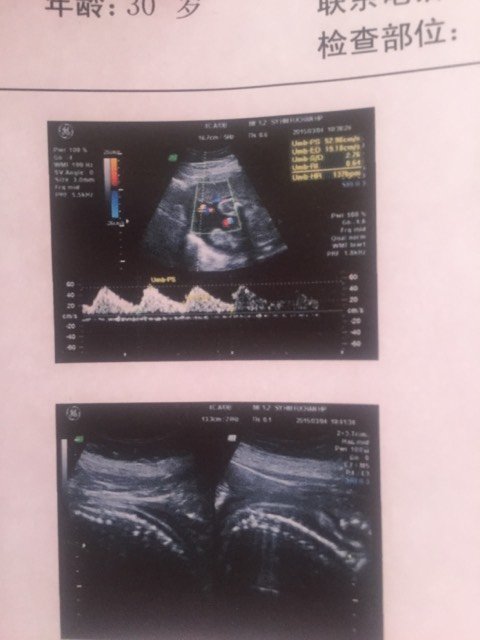

有的宝妈说看四维右上角字母能看出男女,哪位会看给看看 有的宝妈说看四维右上角字母能看出男女,哪位会看给看看 点击展开 健康的宝贝, 2015-03-06 19:32 为您推荐: 其他回答 从b超是不能看出的,也有规定不让给看的,现在男女比例失调了,剩男太多了 cn#BaufLaQLuk 2015-03-06 20:21 不科学的… 小甜猫 2015-03-06 20:07 我5个月朋友给我做了b超是女儿 137*****338_L1Pw 2015-03-06 19:54 我要女儿,我儿子都12岁了 137*****338_L1Pw 2015-03-06 19:53 怀孕的周数不样,看的也不一样,我俩的单子是样,只能参考别当真,生下来的时候能告我一声 137*****338_L1Pw 2015-03-06 19:48 加载更多 相关问题 我听说四维右上角看这个就知道男女是真的吗?hjgh1 后面是1是女孩后面是2是男孩 宝妈们帮我看看今天做的四维